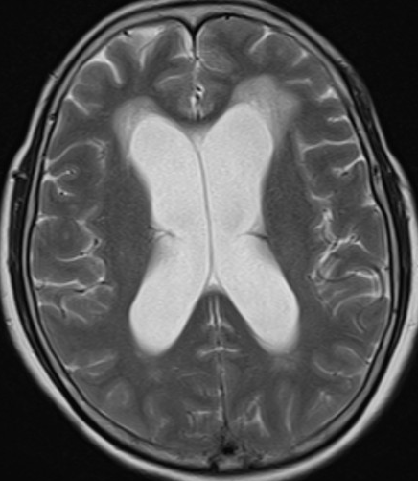

2013-5-16 MRI